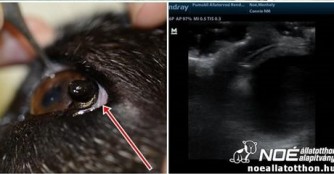

Die kleine Omi Martini, die nach dem Tod ihrer Menschen nach 13 Jahren in die Obhut des NOAH Tierheim Ungarn zurückkam war bei der Augenuntersuchung bei Dr. Rózsa Gabriella in der Tierarztpraxis LotusVet Állatorvosi Rendelő.